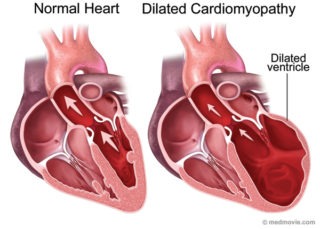

La terapia elettrica di resincronizzazione è in grado di migliorare i parametri clinici, la tolleranza allo sforzo e la qualità di vita del paziente riducendo la dissinergia tipica dei cuori affetti da scompenso cardiaco congestizio in fase avanzata.